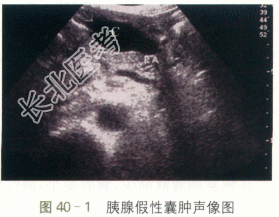

患者,女性,58岁,因“反复上腹部隐痛1月”就诊,伴恶心呕吐。无腹胀、腹泻,不伴皮肤、尿色改变。两月前有急性胰腺炎病史。

ALT341U/L,AST281U/L,AMS6111U/L。

二、影像资料